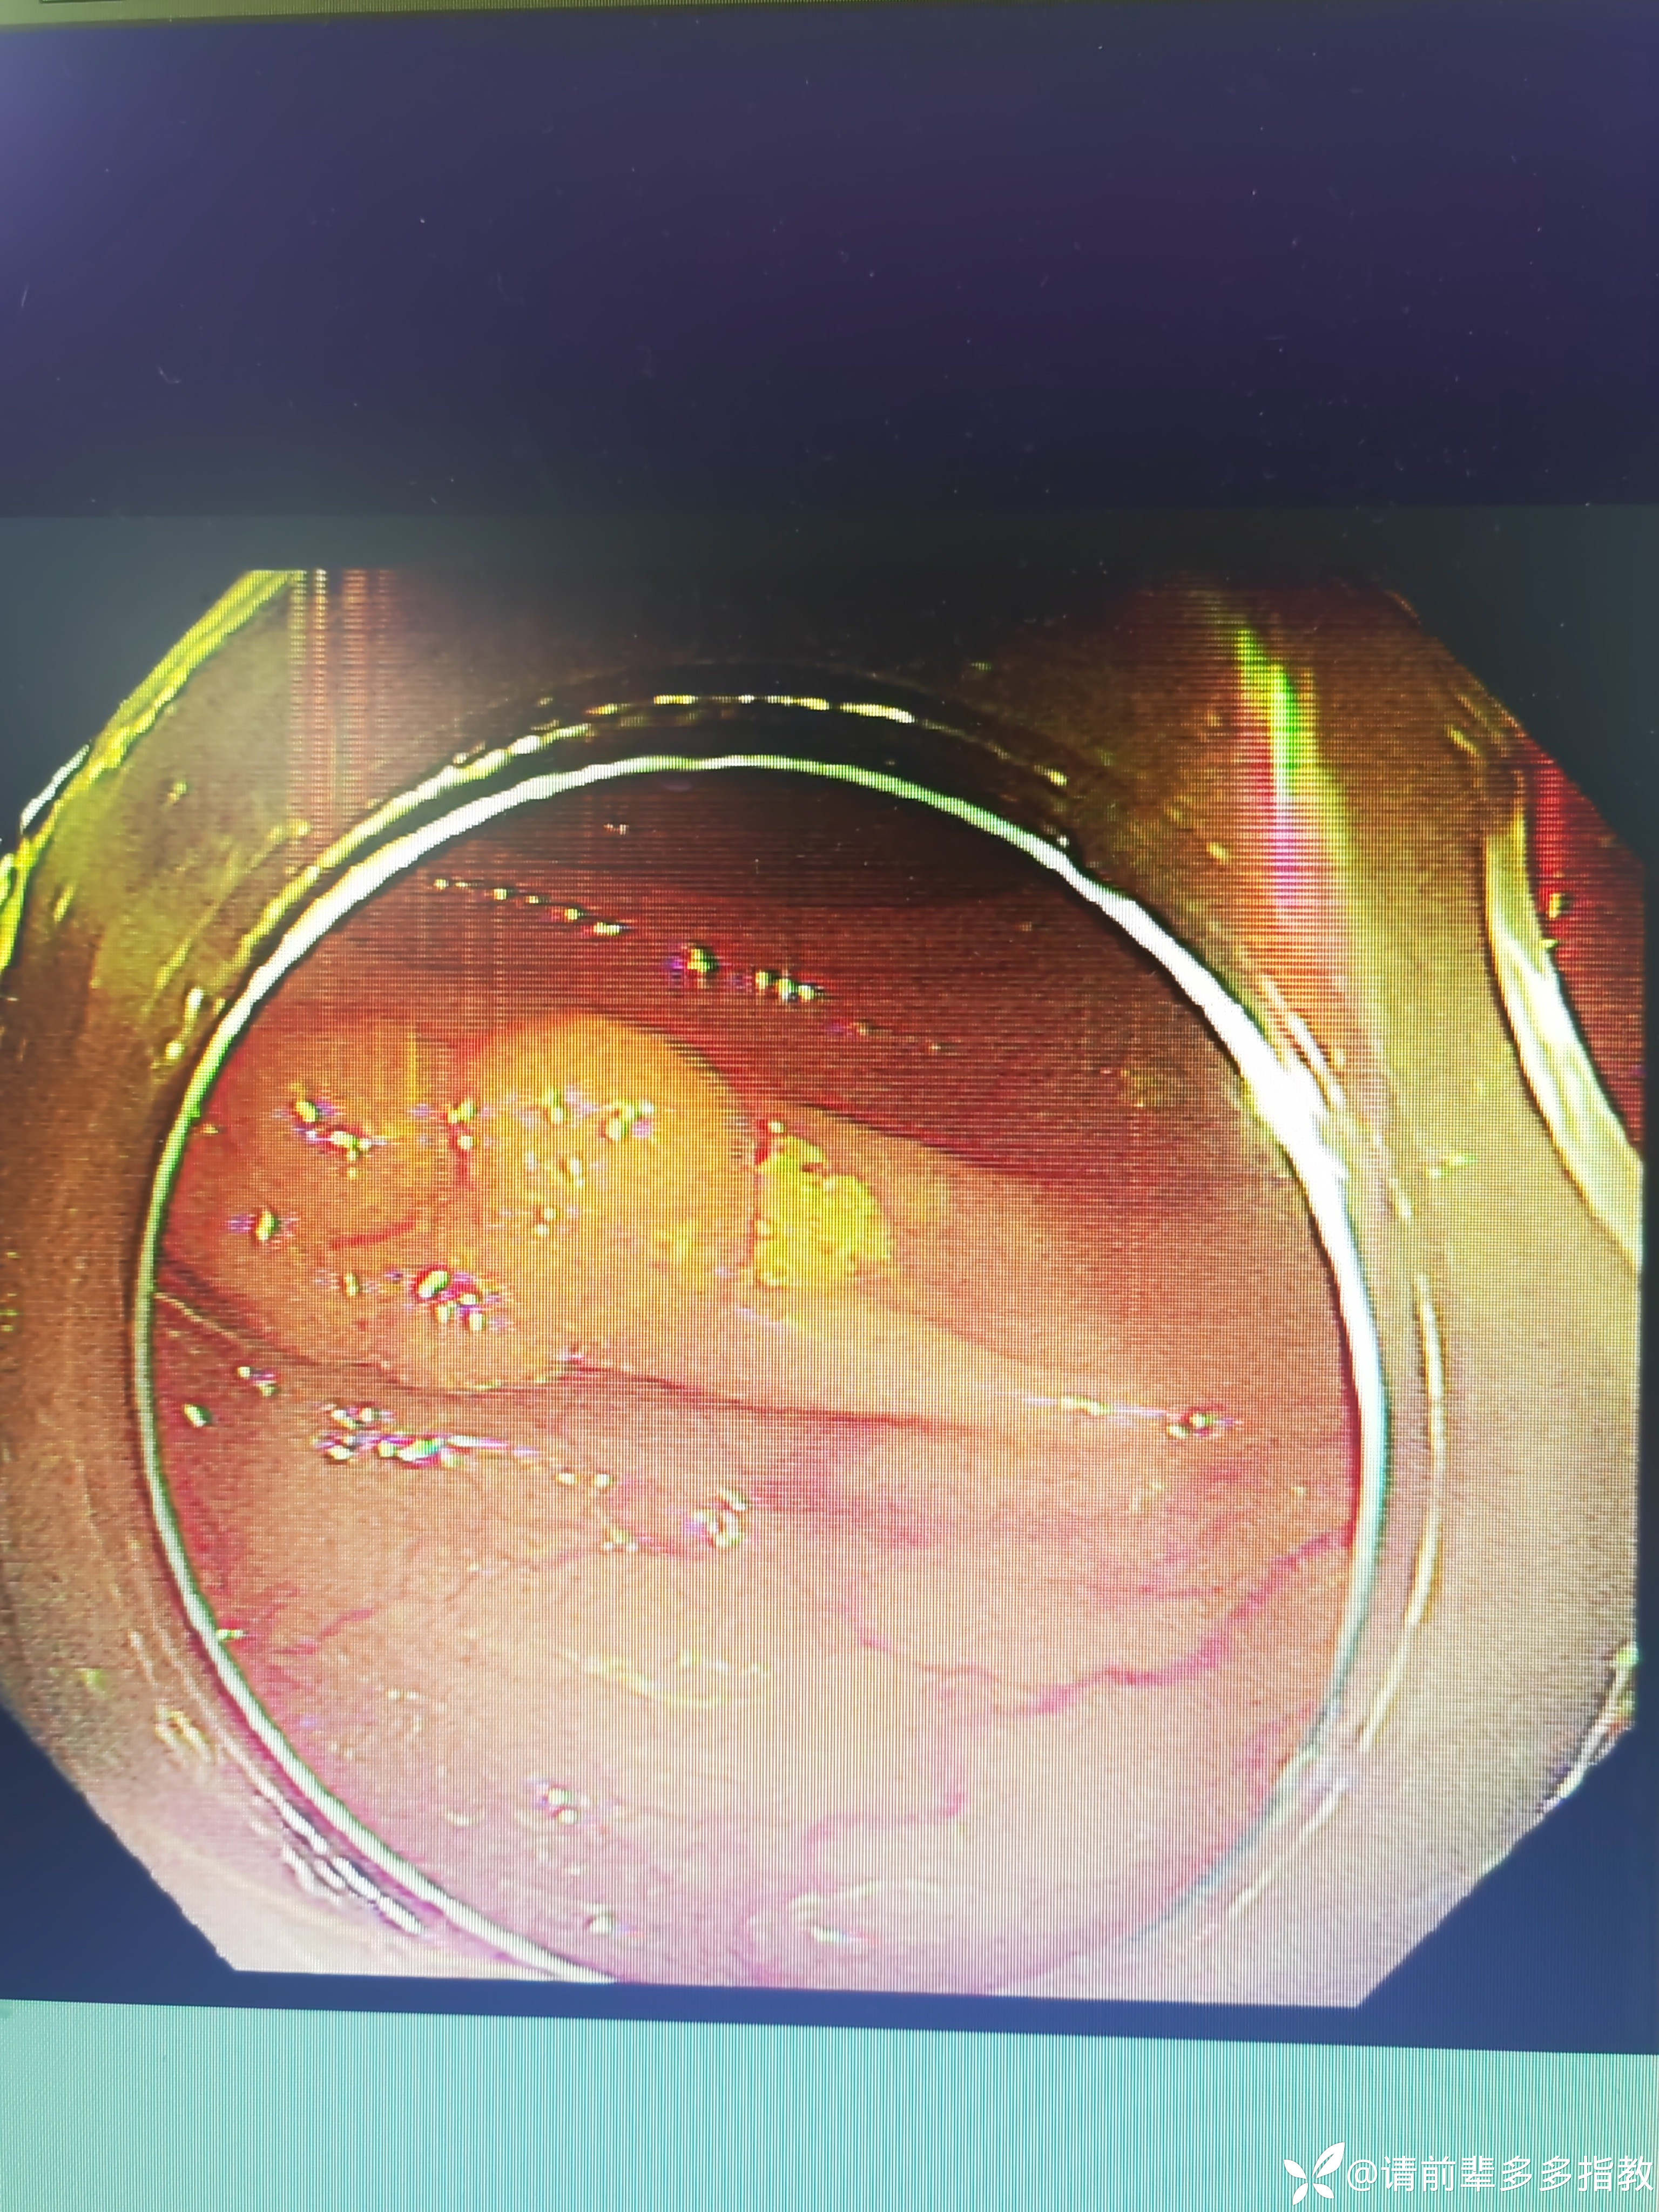

图二:

以上图片报的是1.5cm

但后期进行切除时,手术医师说息肉直径评估过大,图二因为是报的是1.5cm,病人被安排行ESD手术,但最终行的是EMR。此时我才意识到息肉大小准确评估的重要性。(选择合适的治疗方法,充分利用医疗资源)